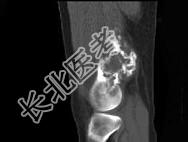

- 单项选择题男,34岁, 大腿下段疼痛2年,可摸到肿块, 结合图像,最可能的诊断是 ( )

A、骨肉瘤

B、软骨肉瘤

C、软骨瘤

D、纤维肉瘤

E、巨细胞瘤